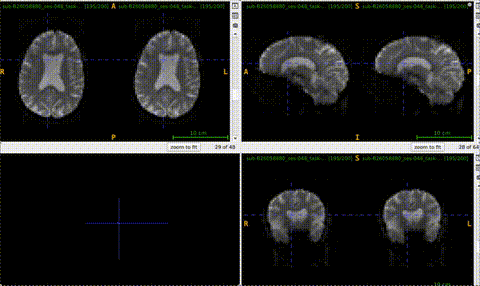

I was wondering, when you get the chance, could you upload example images of your omni-corrected data, one with motion-correction and one without?

for_neurostar

Sorry, I completely missed your message!

It’s a bit tricky to visualize motion, so I’ve uploaded a GIF. On the left is the omni-corrected bold w/ motion correction, and on the right is the omni-corrected bold w/o motion correction (the one I provide to fMRIPrep)